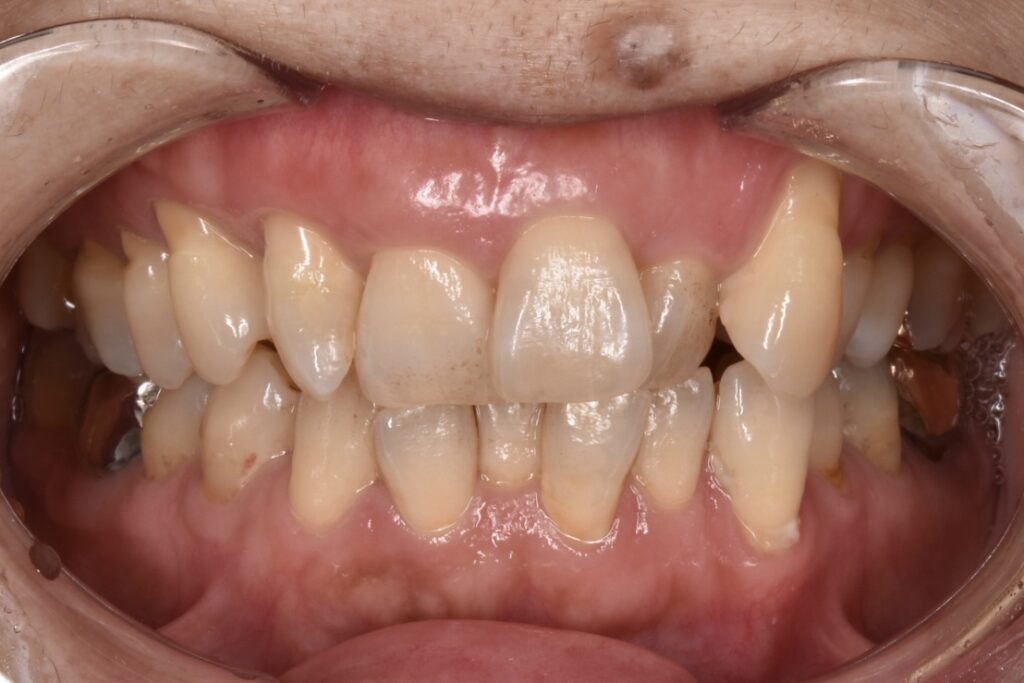

矯正前

前歯を中心に叢生(ガタガタ歯並び)がみられます。

矯正前の横顔や正面、咬合面の写真です。